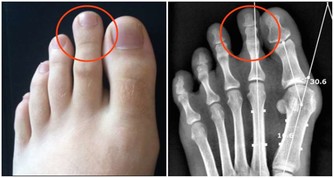

我們每個人對炎症都不陌生,手上不小心劃傷的傷口可能會發炎,感冒的時候扁桃體可能發炎,吃壞了肚子會有腸炎,還有令人感到難纏的關節炎……總之,全身各個器官組織都可能出現炎症,只是或輕或重罷了。

雖然炎症能在受傷的時候保護我們,但大家可能不知道,慢性炎症是非常危險的,它是包括心髒病、癌症在內的致命疾病的誘因。所以,在日常生活中吃一些抗炎食物,不僅可以幫我們減輕炎症帶來的疼痛,也有助於身體健康。